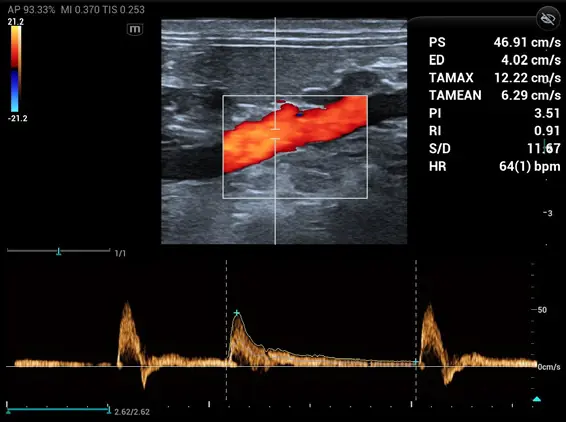

Mikrovasküler veya karmaşık akım paternlerinin görselleştirilmesini geliştiren yenilikçi bir teknolojidir. Mindray Animal’a özgü gelişmiş görüntü işleme algoritmalarıyla, akımın detaylı olarak izlenmesine olanak tanır. HR Flow, hem Renkli Doppler hem de Power Doppler modlarında uygulanabilir.

Tek dokunuşla vasküler yapı görüntülemesinde hızlı ve akıllı optimizasyon sağlar. Smart Track, Renkli, Power Doppler ve PW spektrum modlarında otomatik izleme yaparak zaman alan manuel ayarları ortadan kaldırır.